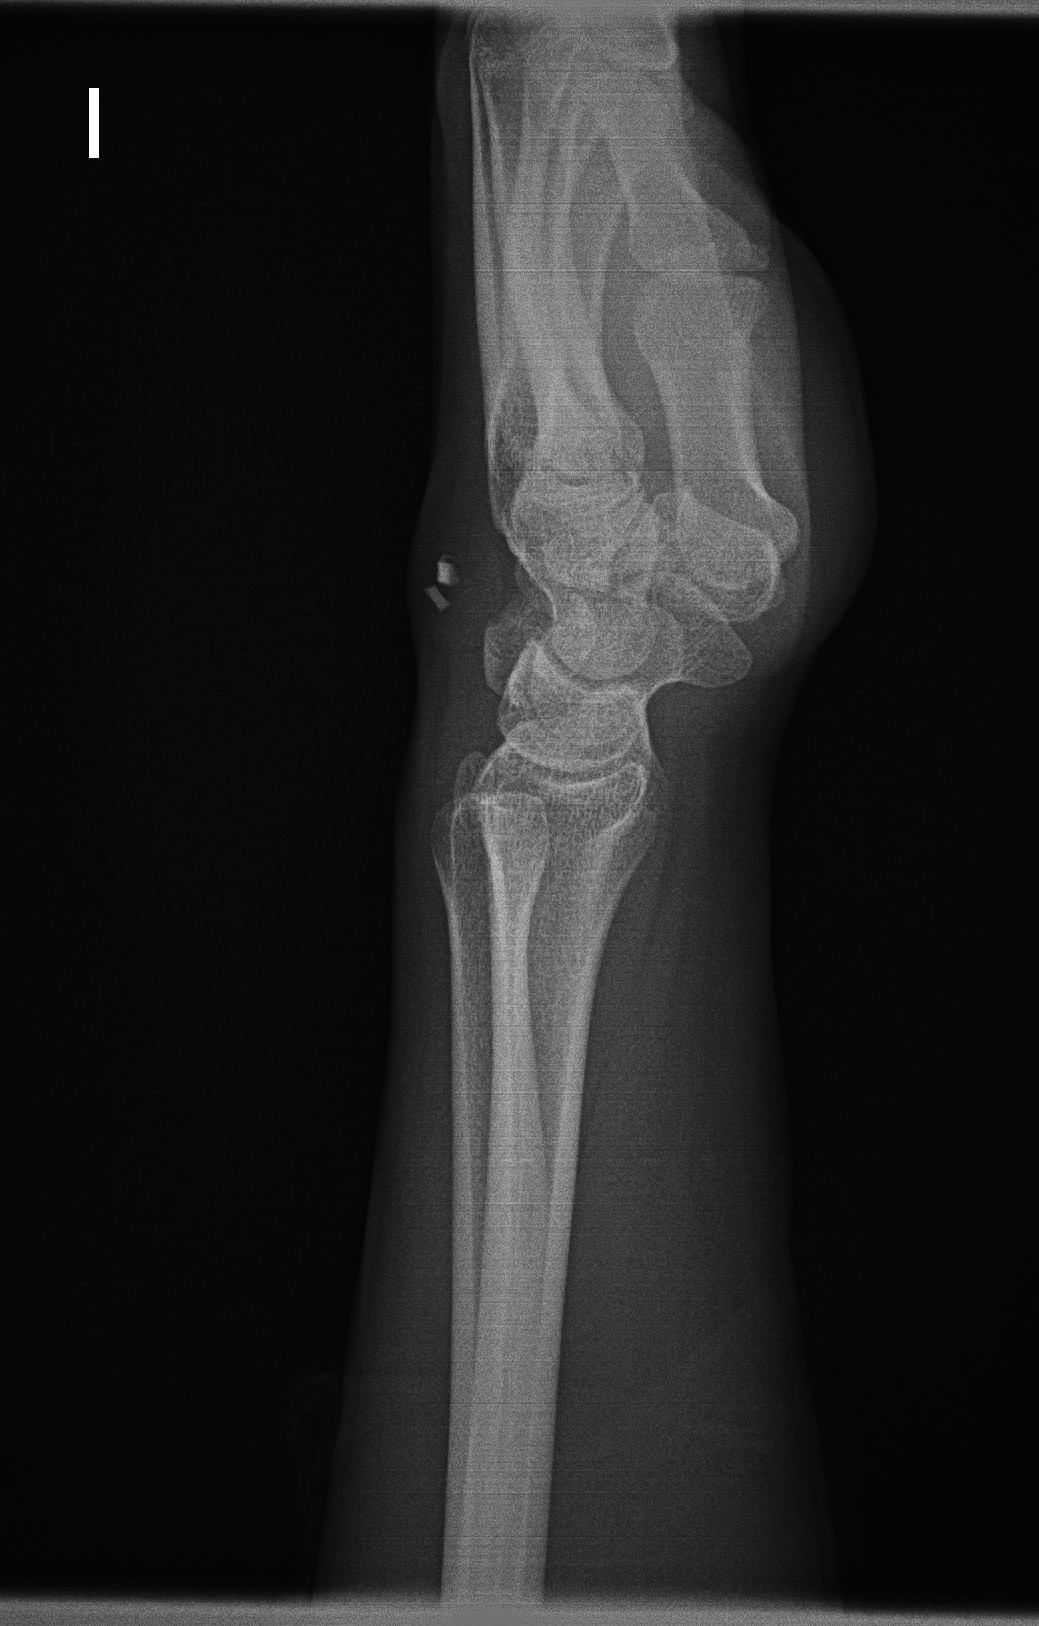

Realizamos Rx en la que se observa dos imágenes radiopacas en partes blandas del dorso de la mano.